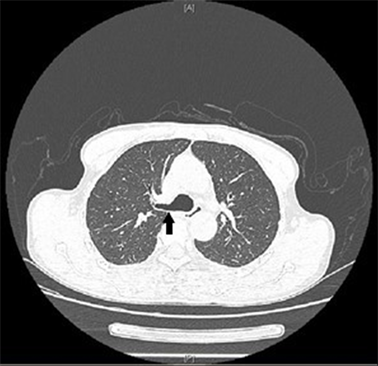

纤支镜下可观察到在隆突两侧各有一支气管开口,隆突上方右侧有一右肺上叶气管开口,考虑为TB(见图1)。查看患者术前CT示:在CT图像165(image,im165)可见右肺上叶开口于主气道(见图2),在im182可见正常的左右主支气管开口于主气道(见图3),证实该患者为TB。

1.jpg

图1 气管性支气管黑色箭头:隆突白色箭头:异常的右肺上叶开口